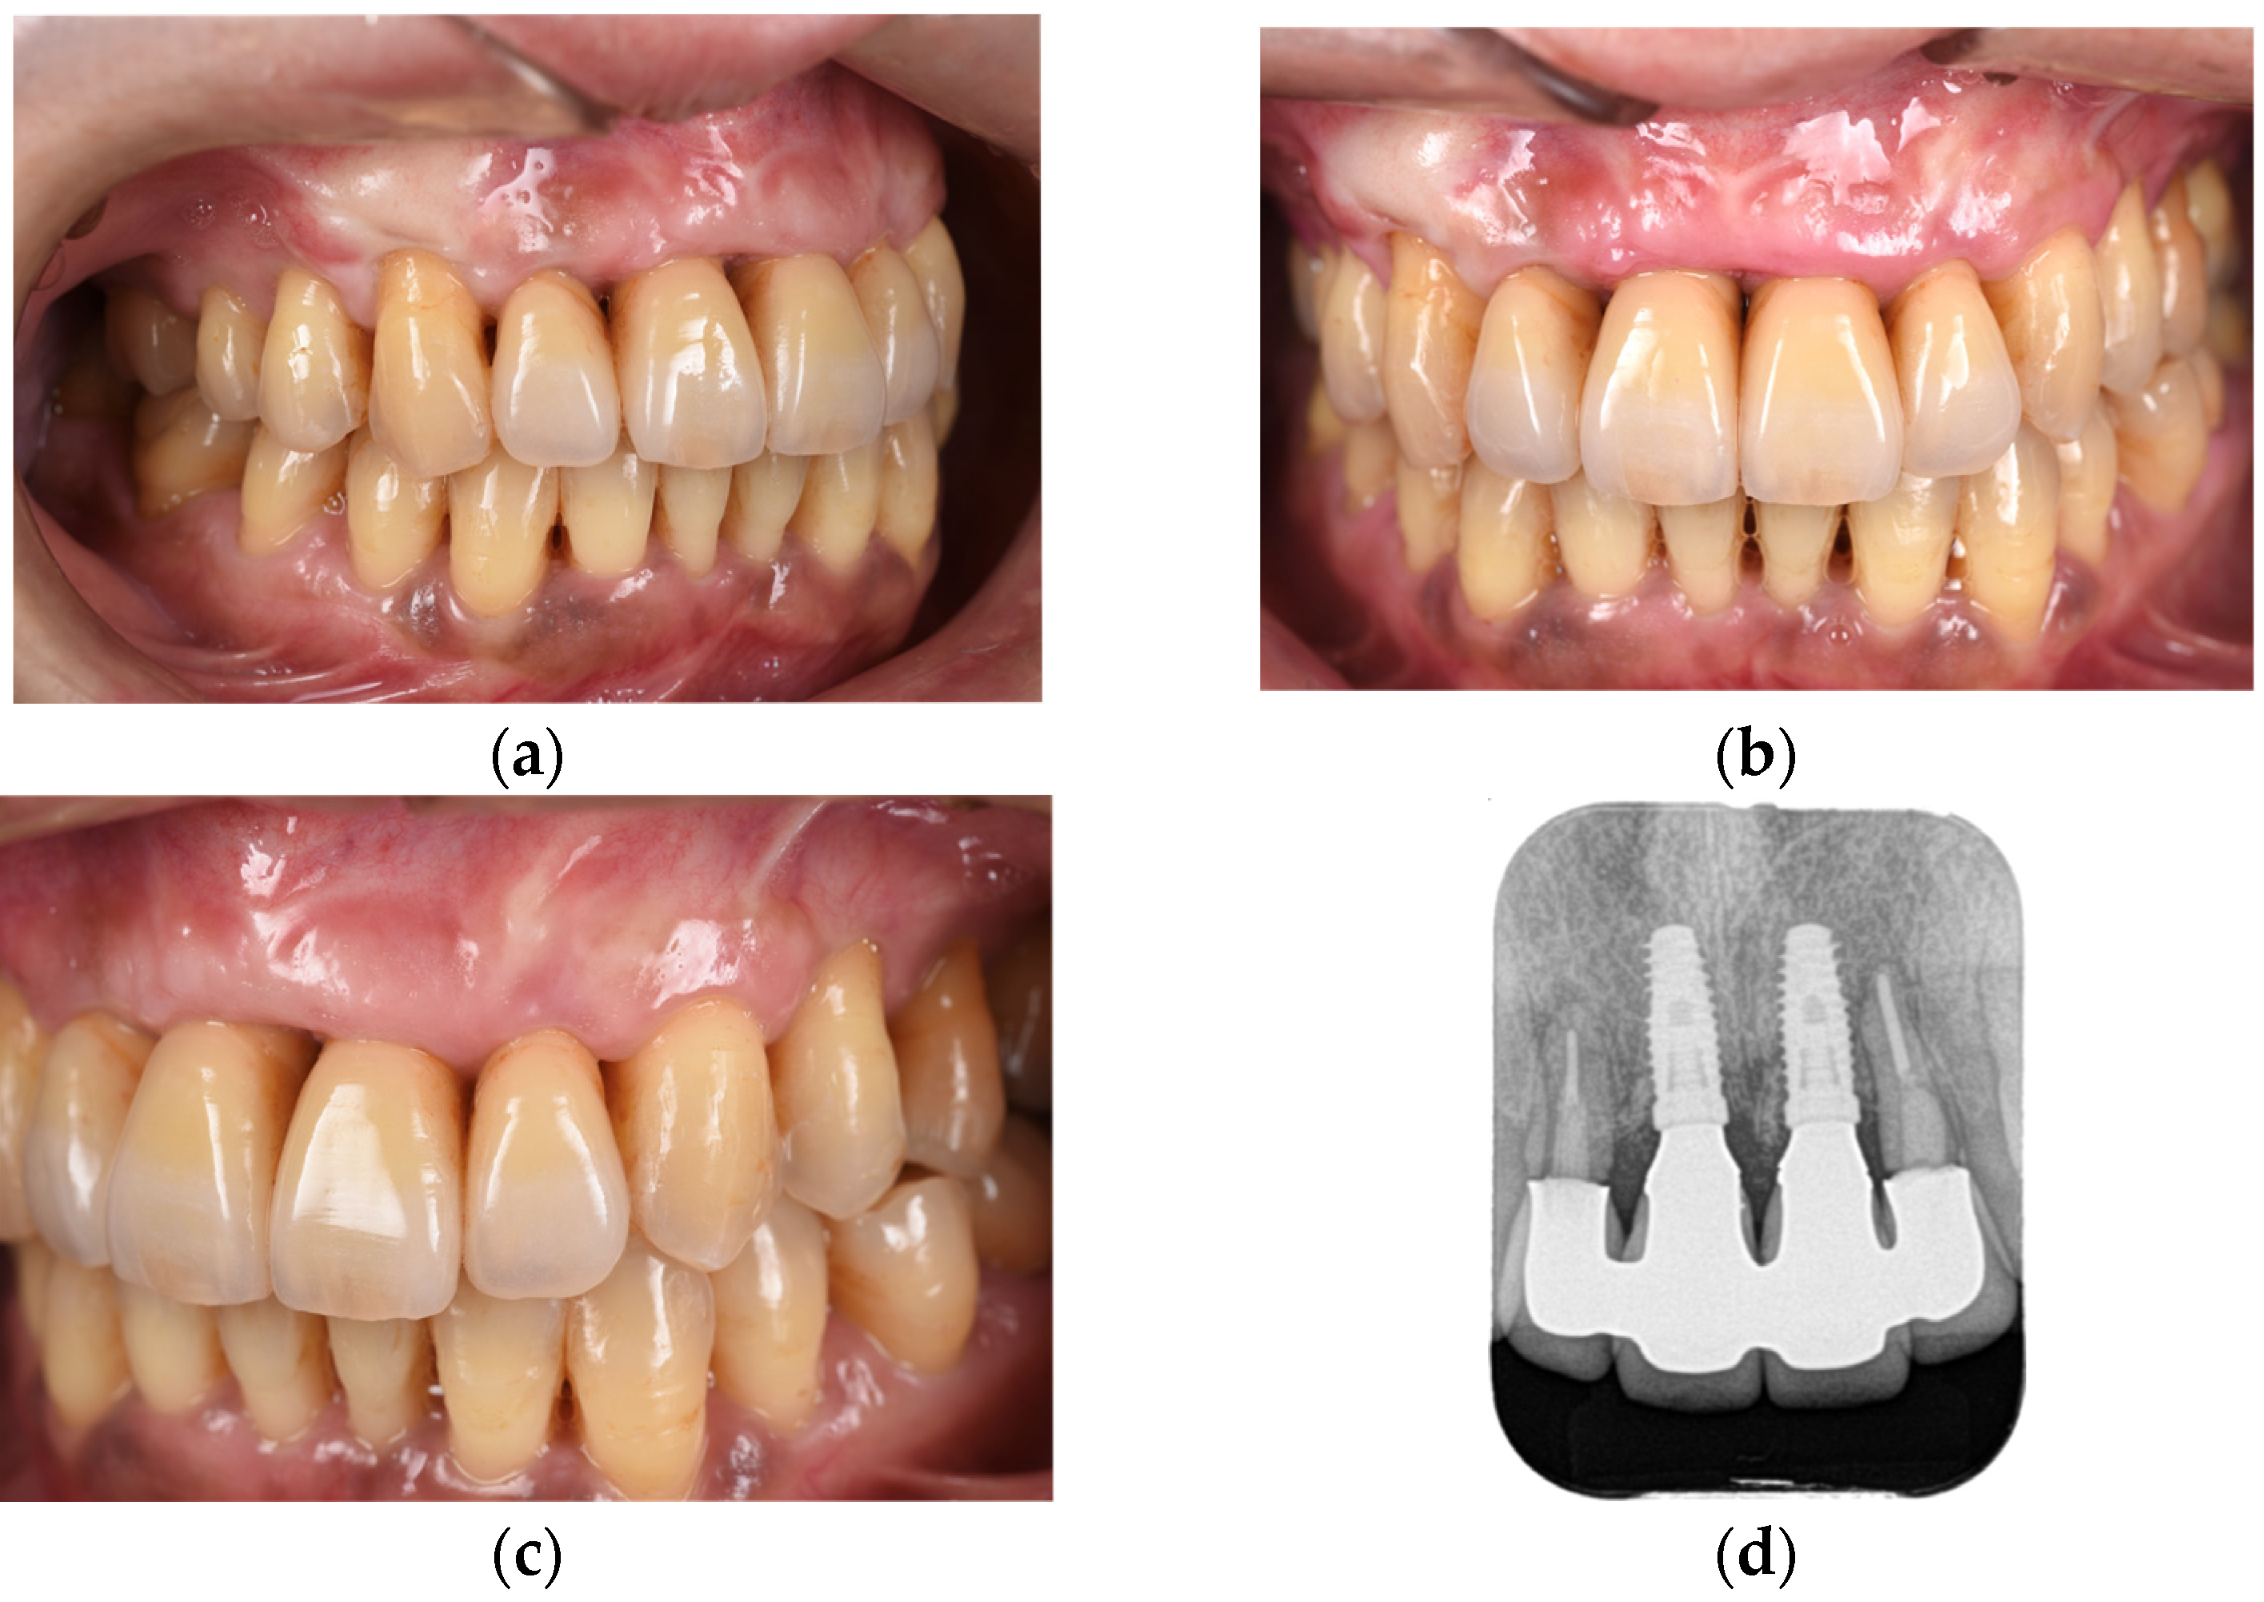

Following the completion of prosthetic treatment, maintenance appointments were scheduled every 3 months. After a 5-year maintenance period, the gingival tissue showed no significant alterations in shape or color, and the adjacent teeth maintained proper functionality (Figure 12). The periodontal status of the patients changed minimally immediately after the placement of the final prosthesis and at the 5-year follow-up (Figure 13).

Figure 12. Right-lateral (a), frontal (b), and left-lateral (c) views and dental radiograph (d) at 5 years postoperatively.

Diagnostics 15 00765 g012